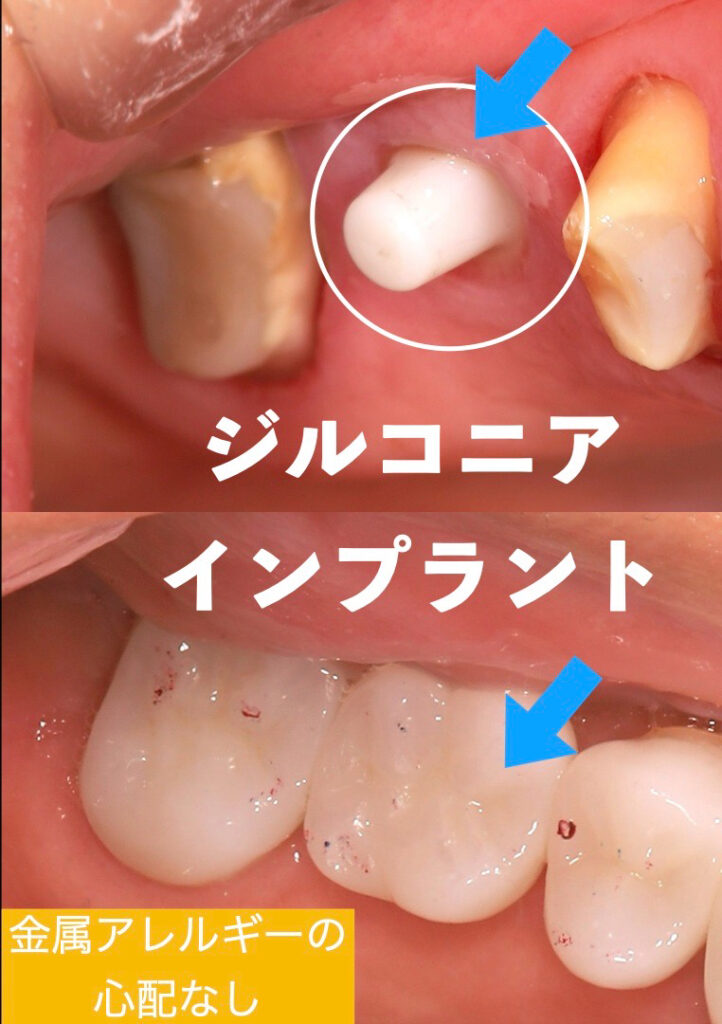

臨床例

治療の経緯

後ろの歯も状態は悪く、何度もインレーが脱離していたので、今回のインプラントをする際に一緒に治療することになりました。一番後ろの歯は残せるのでセラミッククラウンで被せることにしました。

治療経過

治癒は良好で、3ヶ月ほどで仮歯の型取りを口腔内スキャナーで行い、噛めるようにしました。舌や頬を噛まない、問題なくしっかりと噛めることを確認した後、最終的なセラミックの上部構造をセットしました。

治療終了

抜歯から3ヶ月で治療は終了しました。患者様は手術も1回で済み、痛みもほとんどなく大変喜ばれていました。今はメインテナンスに半年に1度、定期的に来院されており問題なくお食事を楽しまれています。何よりも喜ばれたのは手術が一回で済んだのと痛くなかったことだったそうです。